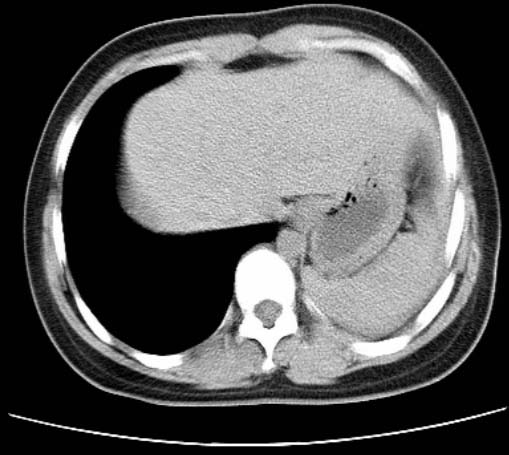

标题: CT25648:求教:是肺发育不全还是结核?

女  20岁。一月前咳血,诊“肺结核”抗痨治疗一月后,咳血停止,现复查。病人精神好。前后ct片对比未见明显变化。既往体检“正常”

1)考虑左肺结核并肺不张、支气管扩张。2)纵隔疝。

考虑左肺结核,左肺毁损,纵膈左偏,既往体检正常不可靠,tb一个月也不会这个样子的,有钙化,应该病程较长,冰冻三尺非一日之寒!

左肺发育不全。

考虑左肺结核,左肺毁损,纵膈左偏,既往体检正常不可靠,tb一个月也不会这个样子的,有钙化,应该病程较长,冰冻三尺非一日之寒

结核,左肺毁损。